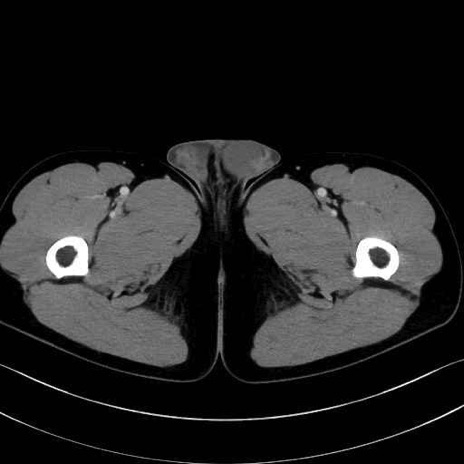

内閉鎖筋 (Obturator internus)